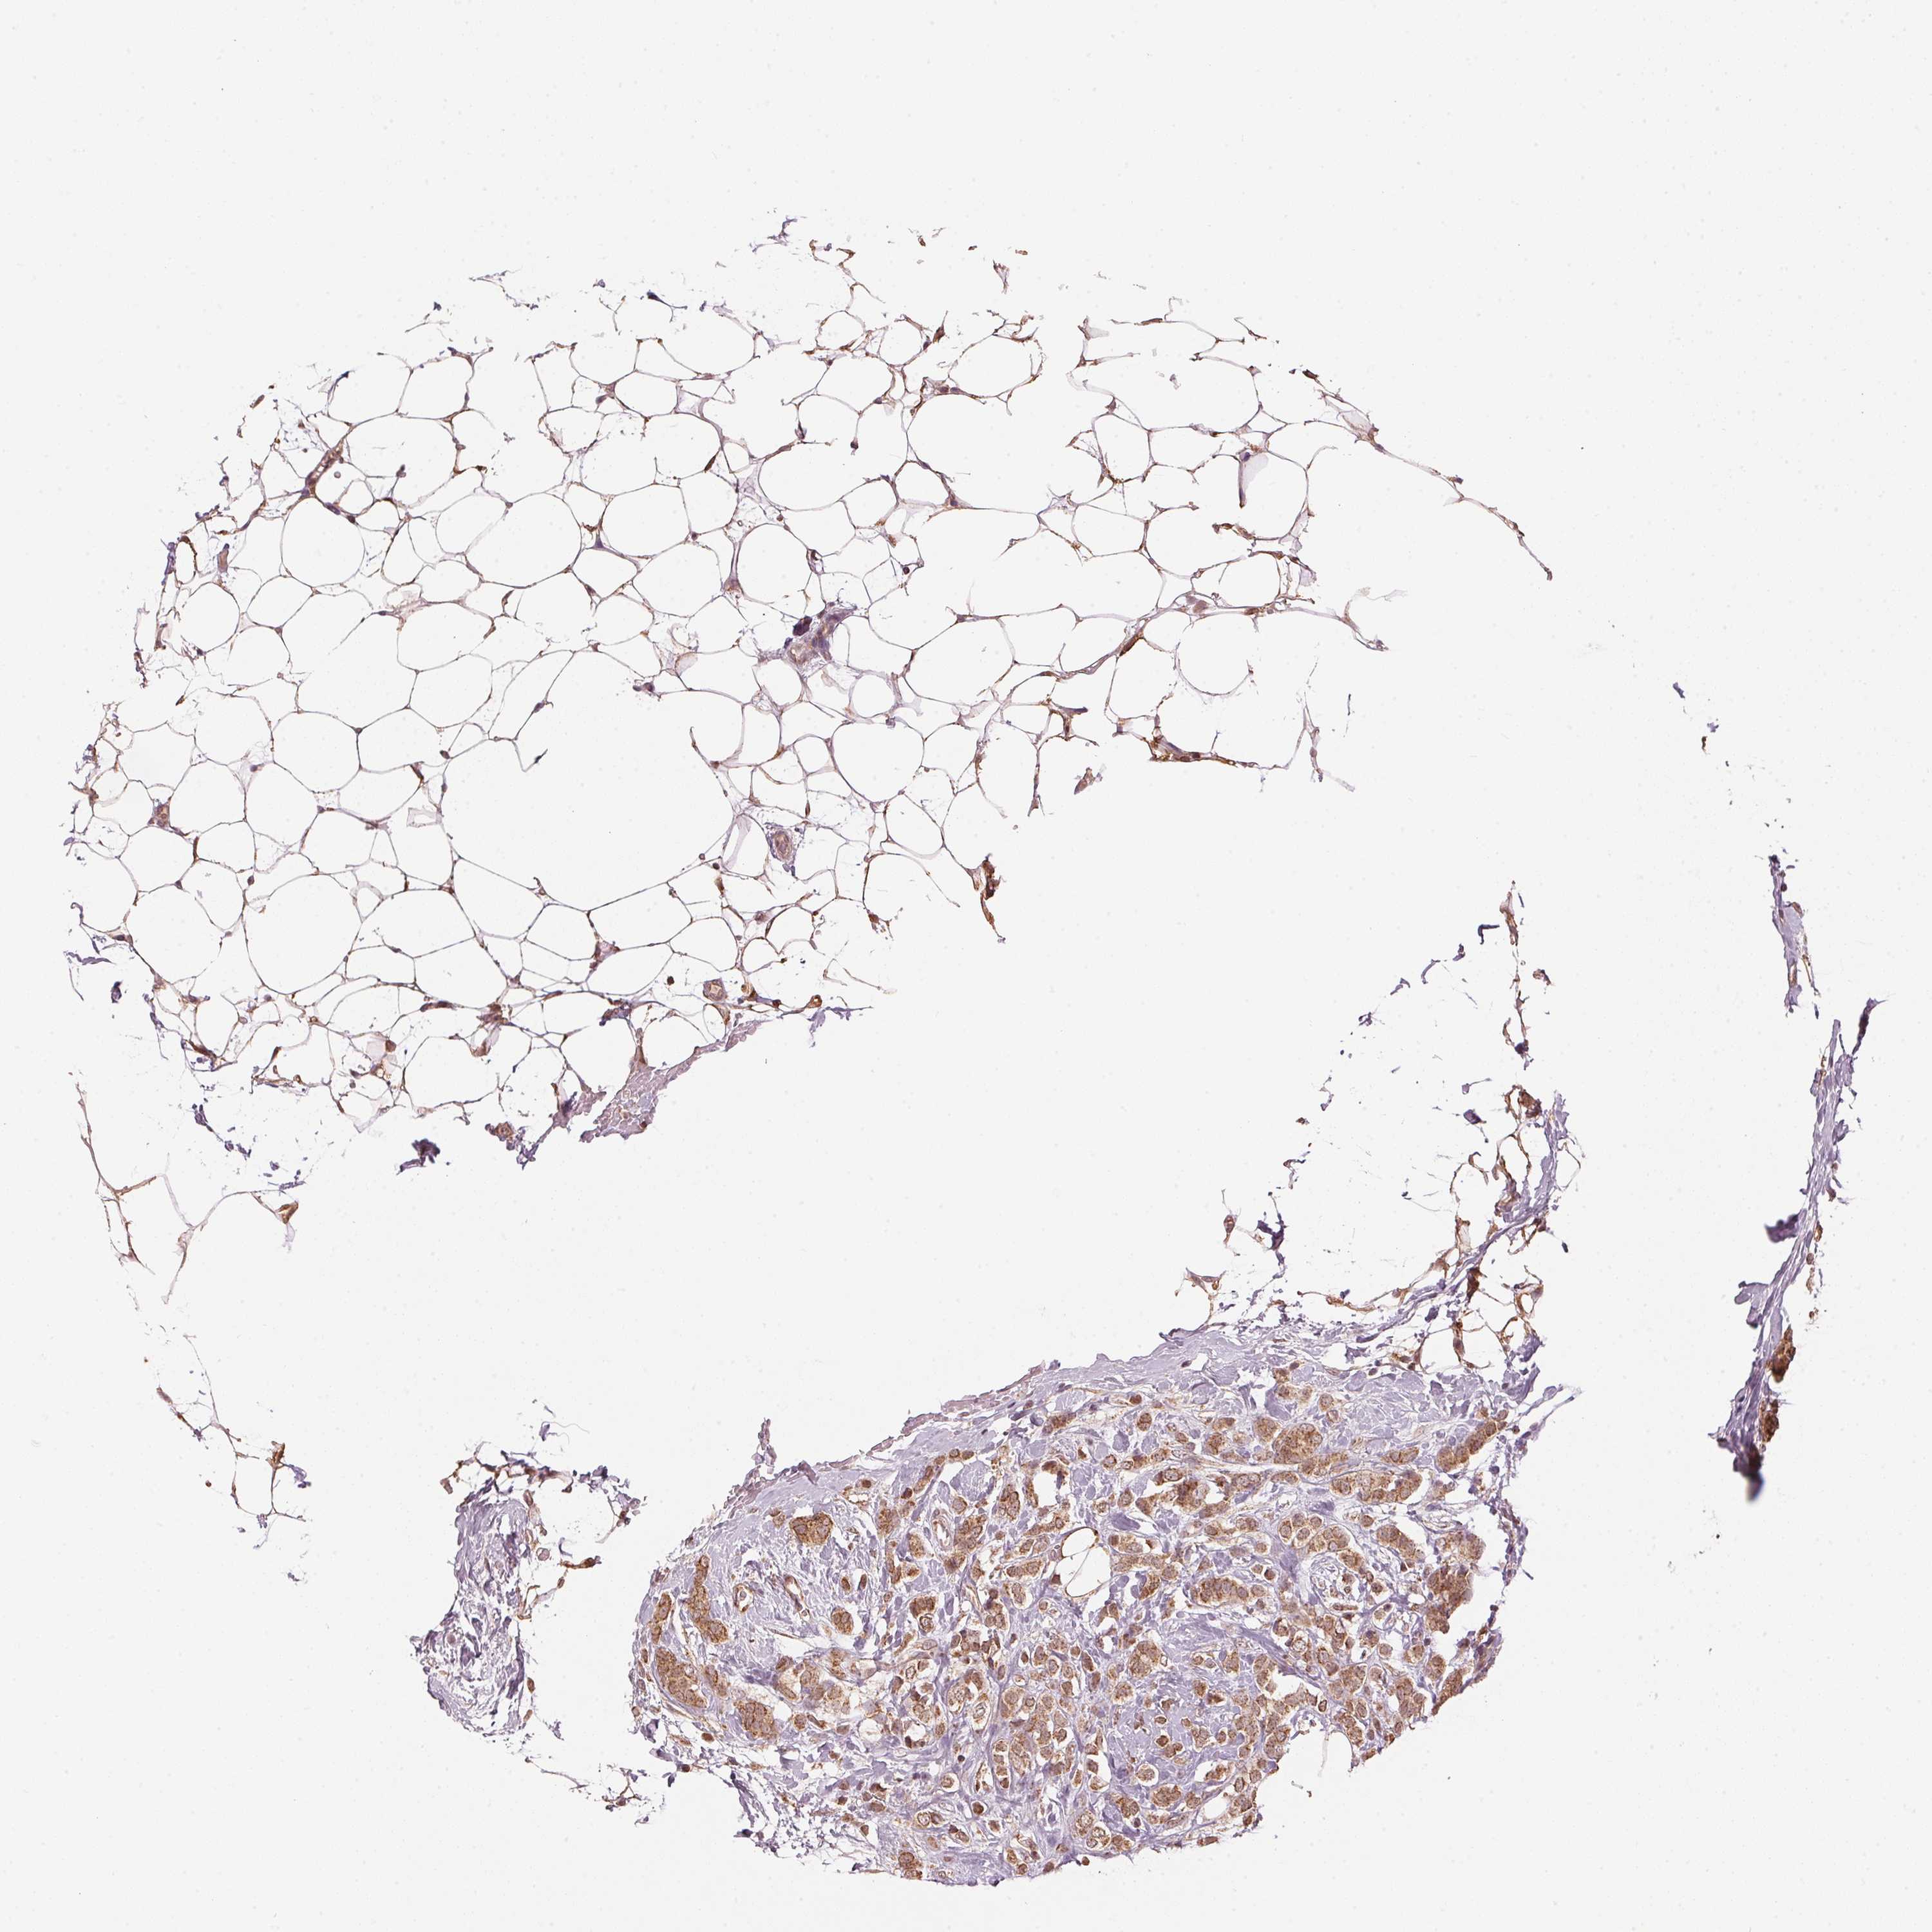

BRCA TCGA BRCA VALIDATION PROTEIN EXPRESSION

Breast cancer

Human cancer